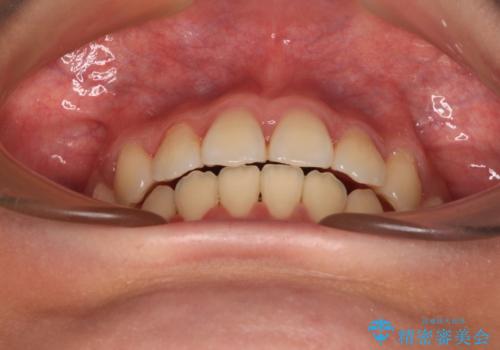

舌の突出癖によるオープンバイトになっていたため、インビザラインによるマウスピース矯正をおすすめしましたが、自己管理の自信がないとのことで、ワイヤー装置による矯正治療を行うこととしました。

舌の突出癖が認められると、上下前歯の隙間を閉じることができません。

舌のトレーニングをしっかりと行っていただくことで、歯列を整えることができます。